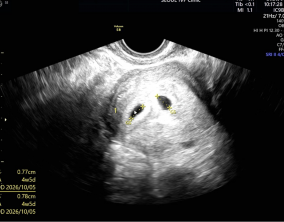

임신 수치 16, 9주차 기적의 기록

서울IVF에서는 단순히 배아 생성과 이식만 해주시는 것이 아니라, 제 생활 전반까지 신경 써주셨습니다. 휴식기에도 그저 기다리는 것이 아니라 항노화에 도움이 되는 링겔을 처방…